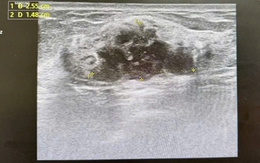

Bị tăng huyết áp và có ngực to như phụ nữ, người đàn ông suýt chết vì khối u lớn "khủng" ở thận

Sống khỏe 2020-08-20T20:28:00Đi khám sức khỏe định kỳ, người đàn ông được chẩn đoán mang bệnh ở gan. Nhưng khi nhập viện điều trị, bệnh nhân lại phát hiện mang khối u lớn khủng khiếp ở thận khiến tính mạng bị đe dọa.